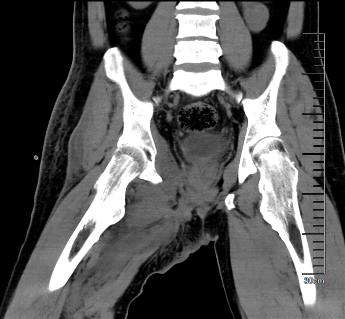

我院骨科王伟东副主任接诊后详细询问了患者疾病发展过程,并为患者做了全身体格检查,仔细查阅了患者的检查报告,综合各方面信息后,诊断患者患有“先天性多发骨软骨瘤病”,并且右耻骨上支的骨软骨瘤已经恶变为继发性软骨肉瘤。目前患者远处脏器尚未出现转移,右耻骨病灶周围解剖屏障尚完整,王主任建议患者手术治疗。

图片 2.png图片 3.png

术前CT